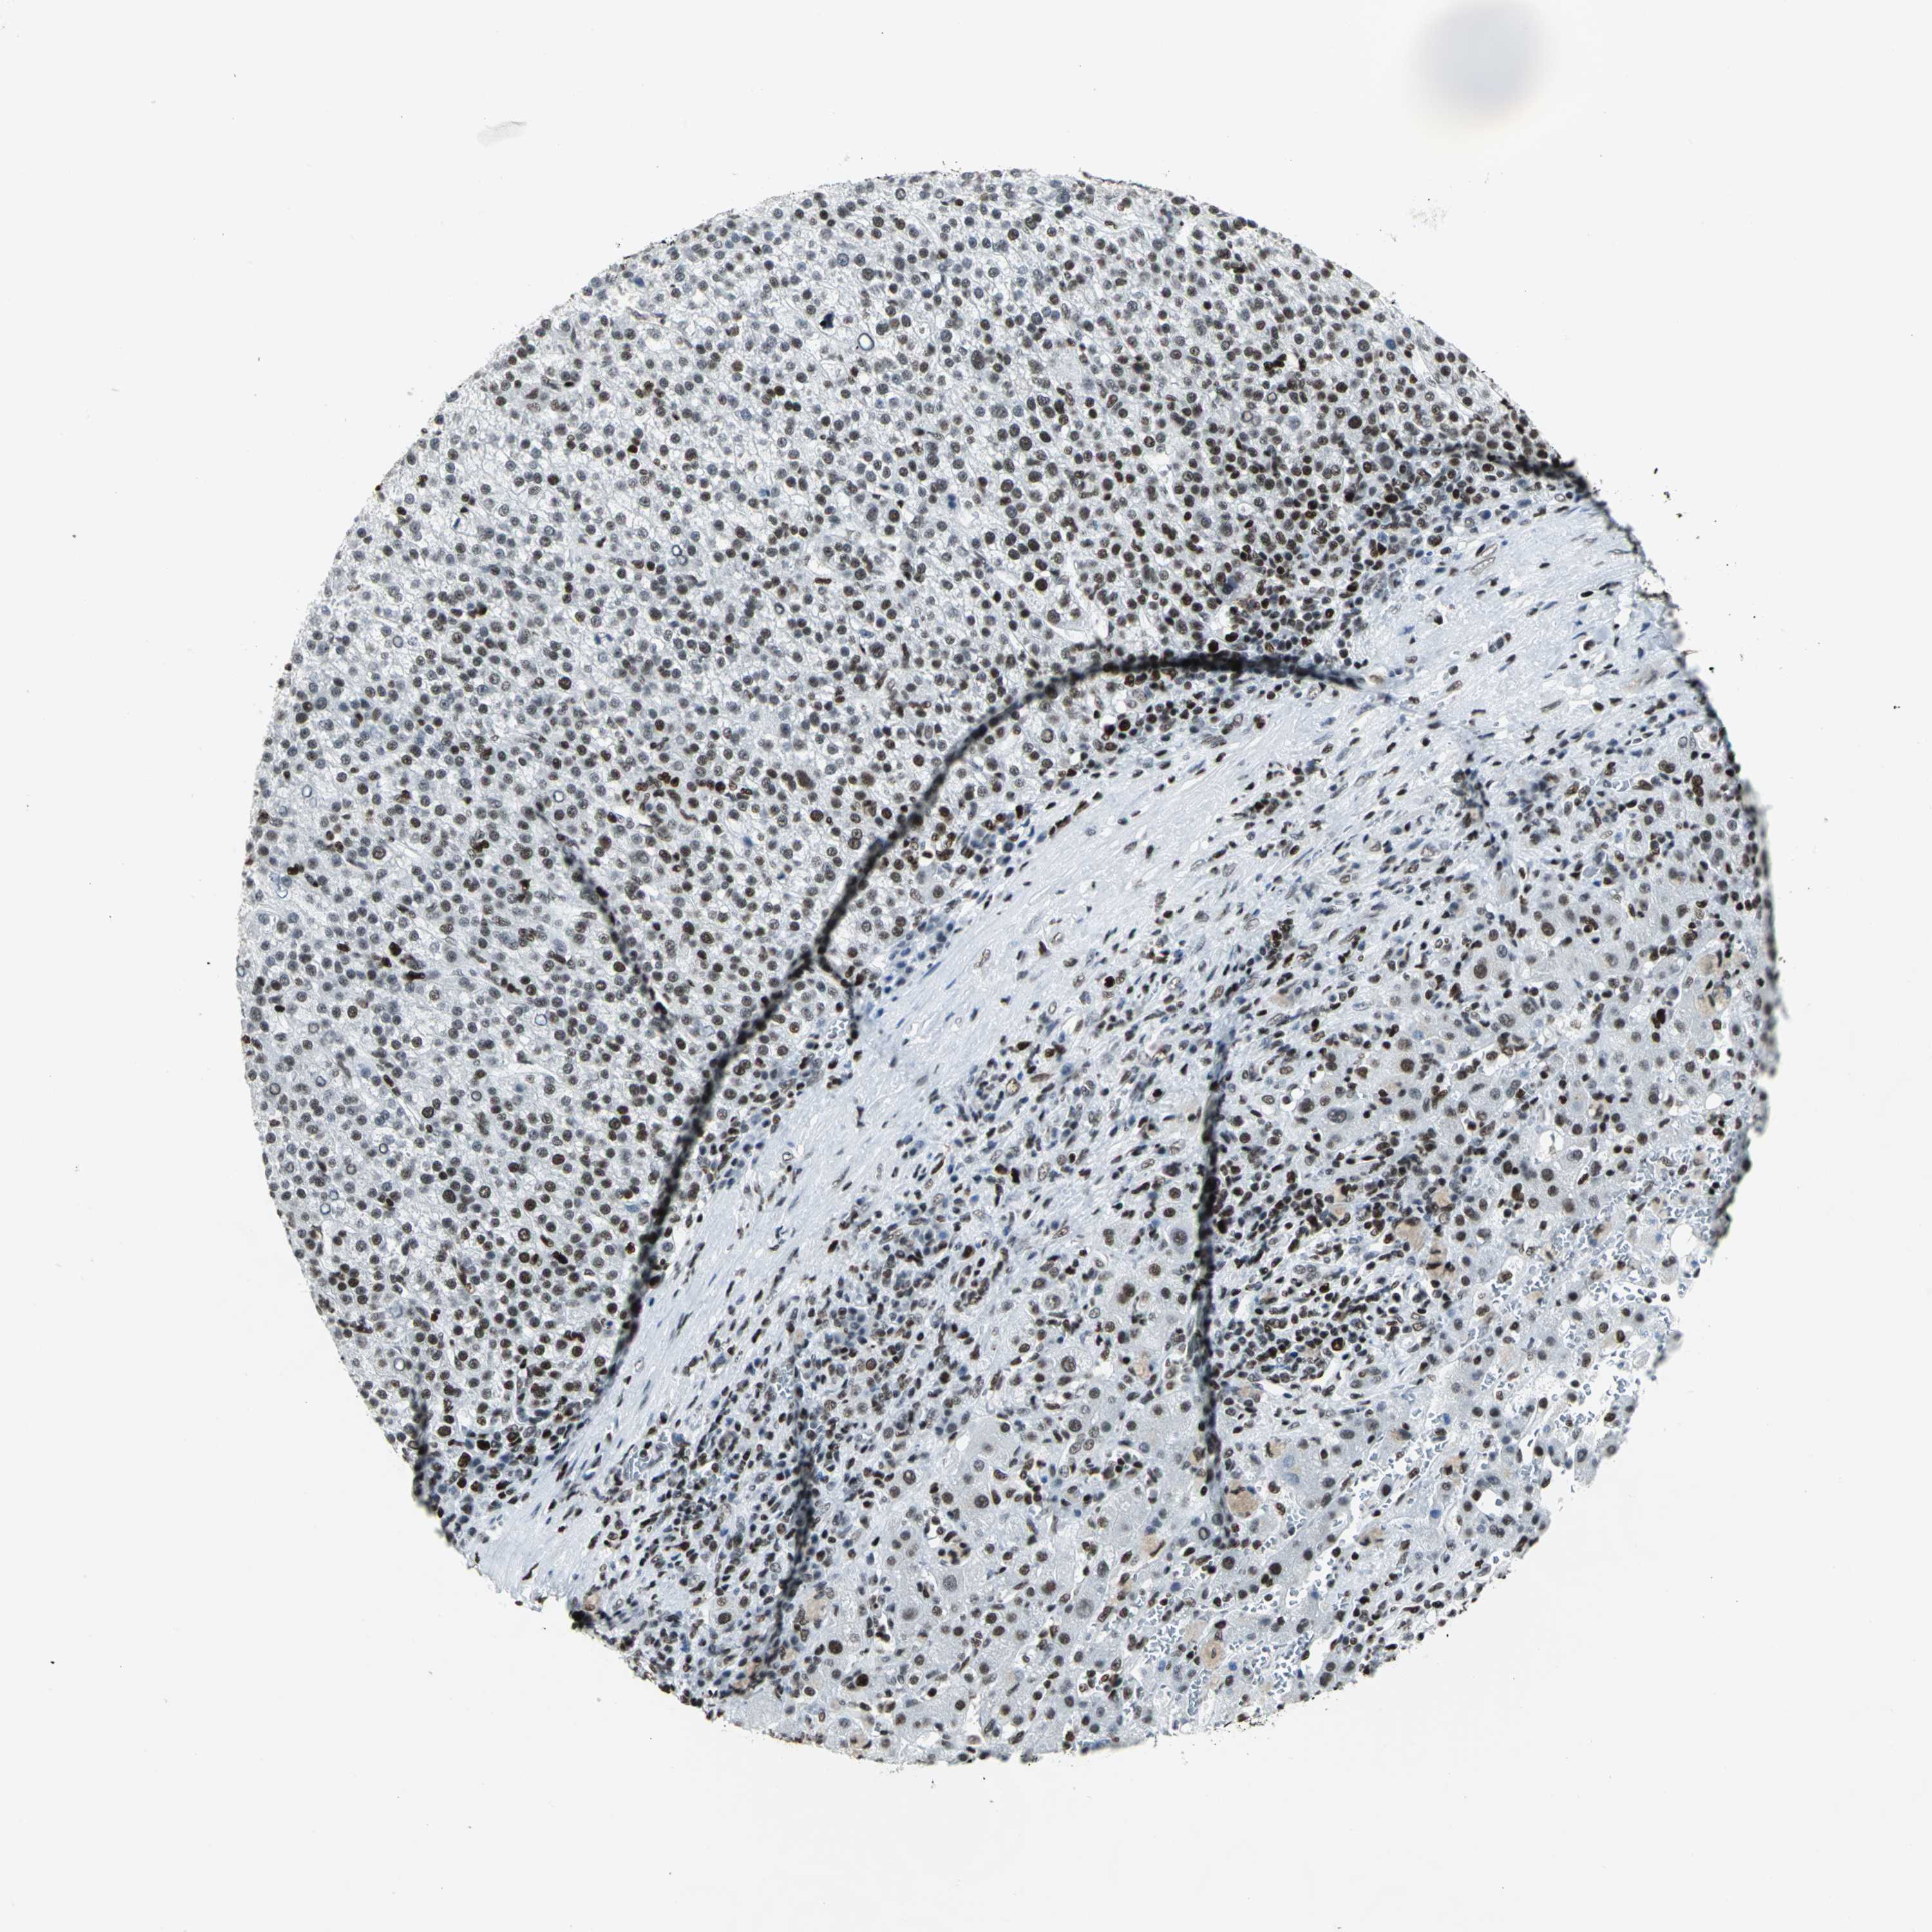

LIVER CANCER - Protein expressioni

A mouse-over function shows sample information and annotation data. Click on an image to view it in a full screen mode. Samples can be filtered based on level of antibody staining by selecting one or several of the following categories: high, medium, low and not detected. The assay and annotation is described here.

Note that samples used for immunohistochemistry by the Human Protein Atlas do not correspond to samples in the TCGA dataset.

Antibody stainingi

Antibody staining in the annotated cell types in the current human tissue is reported as not detected, low, medium, or high, based on conventional immunohistochemistry profiling in selected tissues. This score is based on the combination of the staining intensity and fraction of stained cells.

Each image is clickable and will lead to virtual microscopy that enables deeper exploration of all samples and also displays staining intensity scores, fraction scores and subcellular localization as well as patient and tissue information for each sample.

Antibody HPA004911

Staining

High

Medium

Low

Not detected

Intensity

Strong

Moderate

Weak

Negative

Quantity

>75%

75%-25%

<25%

None

Location

Nuclear

Cytoplasmic/membranous

Cytoplasmic/membranous,nuclear

Cholangiocarcinoma

Carcinoma, Hepatocellular, NOS